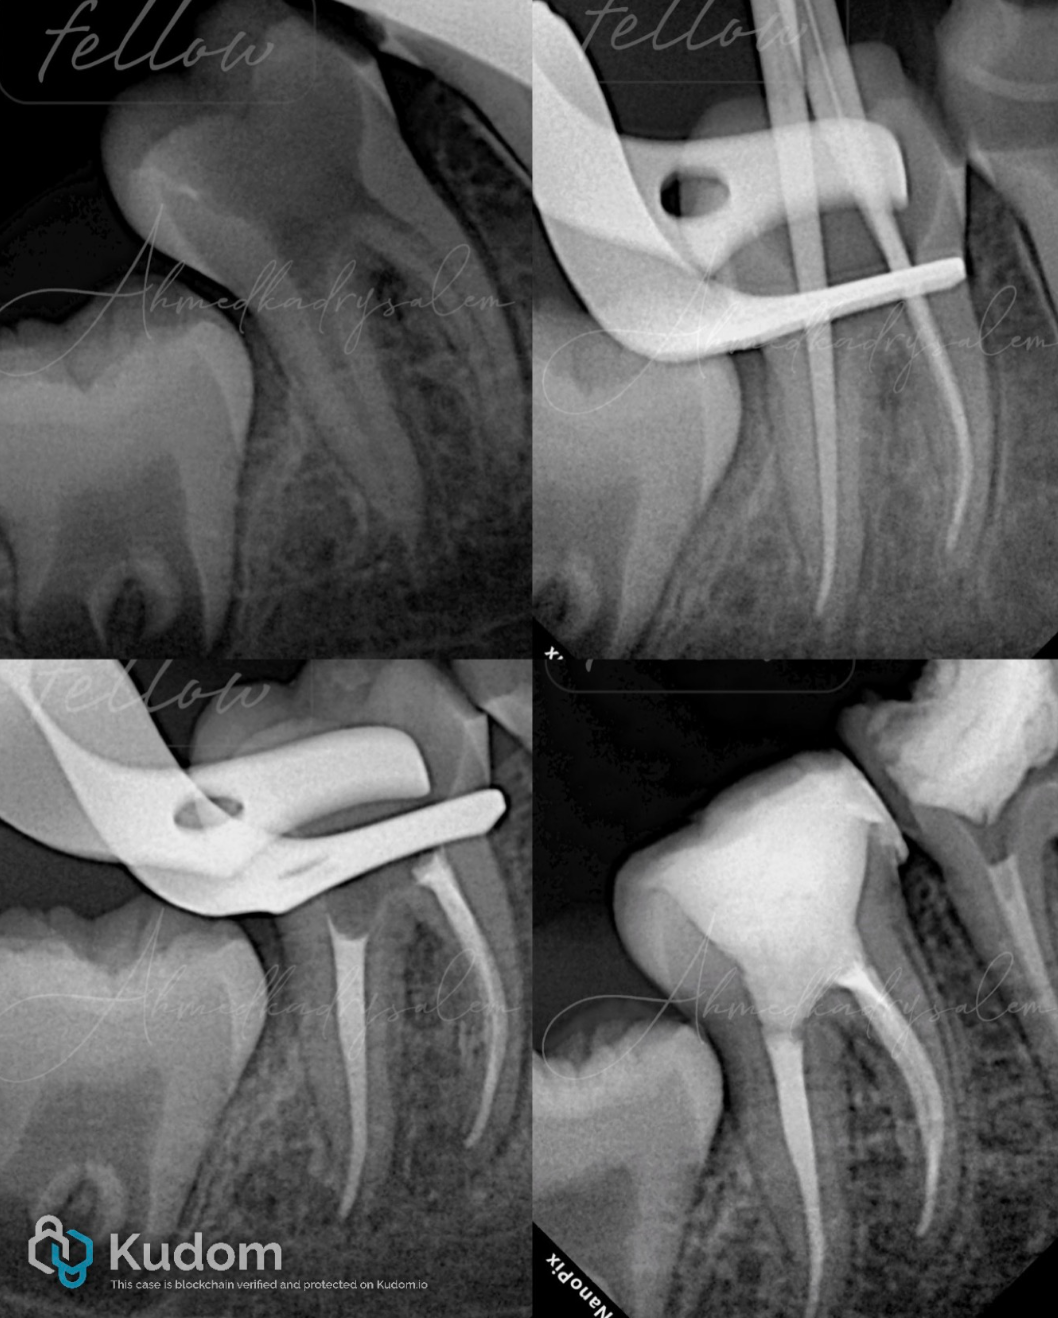

上图 4 完整病例